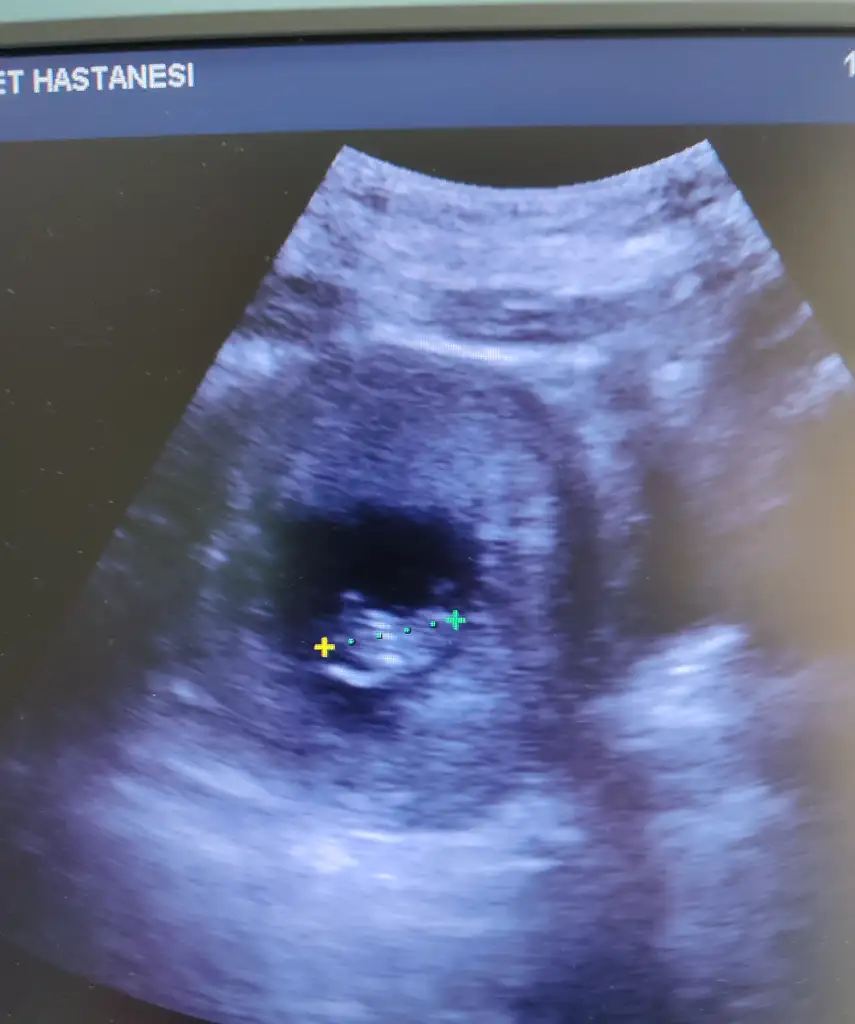

Kalp atışı duydunuz mu? Cuma günü ultrasona göre 7+1 olacağız kalp atışını duymayı ve bebegi görmeyi bekliyorumTeyzeleri biz geldik şimdi çıktım doktordan ayyy gördük bebişimizi7+2 günlüğüz ayyy

Görünür tabikide 7 hafta gayet net duyulurKızlar merhaba

7+1 de karından ultrasonda bebek kalp atışı görünür mü göbeğimde var biraz tecrübe eden var mı ?

Görünüyor dinleniyor da canım ben 7+1 de dinledimKızlar merhaba